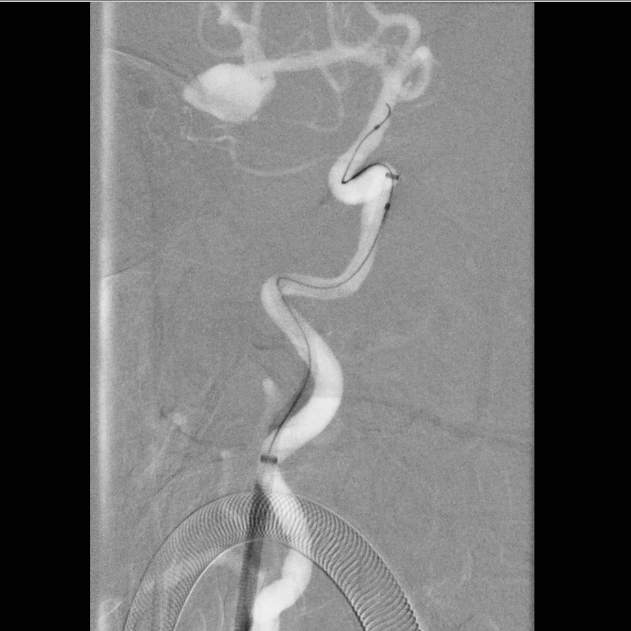

病史:中年女性,新冠感染,颅内动脉瘤破裂,Hunt-Hess 4级

最终,动脉瘤瘤体致密栓塞,各个分支保留良好